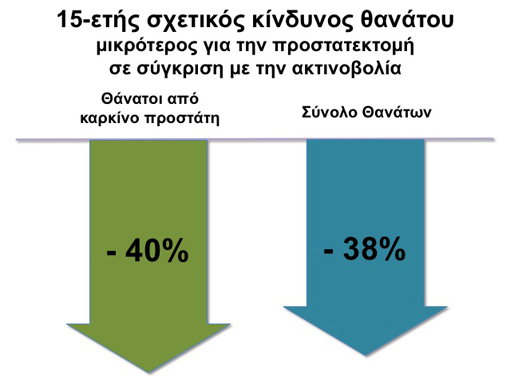

Μία μελέτη σε 3.159 ασθενείς έδειξε ότι 15 χρόνια μετά την θεραπεία, εκείνοι οι ασθενείς που υποβλήθηκαν σε ριζική προστατεκτομή είχαν 40% χαμηλότερο κίνδυνο θανάτου από καρκίνο του προστάτη σε σύγκριση με τους ασθενείς που αντιμετωπίστηκαν με ακτινοβολία.1

Σε μία μελέτη με 844 ασθενείς με εντοπισμένο καρκίνο του προστάτη, οι ασθενείς που υποβλήθηκαν σε προστατεκτομή είχαν υψηλότερα ποσοστά επιβίωσης από καρκίνο του προστάτη σε σύγκριση με τους άνδρες που επέλεξαν άλλες μορφές θεραπείας.2

Results: After adjusting for age, race, tumor grade, comorbid disease, income status, and year of diagnosis, the overall survival rate at 15 years was 35% for conservative management, 50% for radiotherapy, and 65% for radical prostatectomy. The corresponding prostate cancer-specific survival rates were 79%, 87%, and 92%. Patients undergoing radiotherapy or radical prostatectomy had lower overall mortality than patients undergoing conservative management (adjusted relative risk 0.67 for radiotherapy and 0.41 for prostatectomy; P <0.001). The increase in the survival duration was 4.6 years with radiotherapy and 8.6 years with radical prostatectomy.